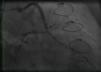

Case reportA 50-year-old white male with hypertension, hyperlipidemia and coronary artery disease had coronary artery bypass surgery with a left internal mammary artery to left anterior descending artery graft and reverse saphenous graft to the first obtuse marginal (OM1) 13 months previously. He had had a non-ST segment elevation myocardial infarction two months previously with placement of a drug-eluting stent (DES) in the right coronary artery (RCA). He also had 90% focal stenosis at the distal anastomosis of the SVG to the OM1 on coronary angiography (Figure 1). This graft was also filling the left circumflex system retrogradely. The patient continued to have class 2–3 angina since his PCI to the RCA. He had been compliant with his medications: aspirin 81 mg daily, clopidogrel 75 mg daily, carvedilol 12.5 mg twice daily, Lisinopril 5 mg daily, rosuvastatin 40 mg daily, gemfibrozil 600 mg twice daily. With this clinical picture, he was scheduled for percutaneous intervention of the distal anastomotic lesion of the SVG to OM1 graft. The latter was engaged with a 6-F Amplatzer Left 0.75 guide catheter and after therapeutic anticoagulation was achieved with heparin, a Balance Middleweight guidewire (Abbott Vascular) was placed in the distal OM1. The lesion was then dilated with a 2.5 mm × 12 mm Apex balloon catheter (Boston Scientific Corporation) at 12 atm with full balloon inflation. This reduced the lesion from 90% to 40% stenosis. A 2.5 mm × 8 mm Promus stent (Boston Scientific Corporation) was then deployed at 15 atm across the lesion into the native OM1 distally and the stent balloon was reinflated proximally at 18 atm, with full expansion of the stent (Figures 2 and 3). The stent was then post-dilated with a 3.5 mm × 6 mm Sprinter Legend noncompliant balloon (Medtronic) inflated at 12 atm in the anastomosis and at 18 atm in the vein graft. Initially, the stent appeared to have expanded well (Figure 4), but, while more angiographic images were being taken, the stent recoiled in the vein graft at the distal anastomosis with reappearance of 80–90% focal stenosis inside the stent (Figure 5).